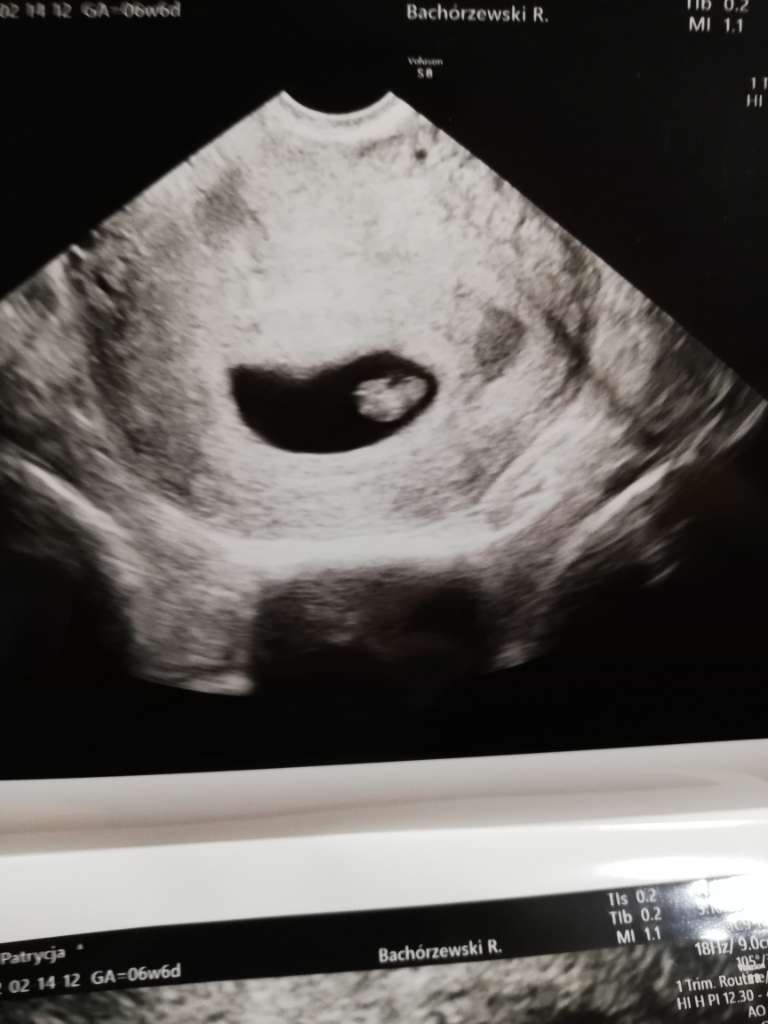

A tu zdjęcia z dziś 😍

Załączniki

• 2cc92550-dea5-4b95-9262-be4bbf93084c.jpg

2cc92550-dea5-4b95-9262-be4bbf93084c.jpg

71,6 KB · Wyświetleń: 99

tak, 6t6d. Ma wielkość 1,06cm 😉 mój ginekolog faktycznie ma dobry sprzęt 🙂 pewnie i u Ciebie będzie widac już co nie co😉który to będzie tydzień?